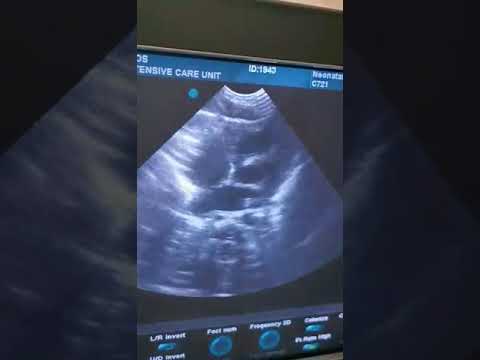

Στο παρακάτω βίντεο φαίνεται η στιγμή που η καρδιά του βρέφους χτυπά ξανά χωρίς μηχψανική υποστήριξη: